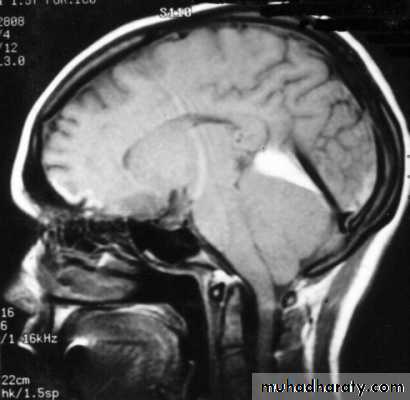

The CT and/or MRI scan will show no cause for the papilloedema and the ventricles will often be smaller than usual.

Digital subtraction cerebral angiography or magnetic resonance venography may be performed to exclude thrombosis of a venous sinus as the cause.

If the CT scan or MRI shows no mass or lesion a lumbar puncture is usually performed; the pressure will be raised. CSF examination is normal in benign intracranial hypertension but biochemistry and cytological investigations should be performed to exclude underlying pathology.